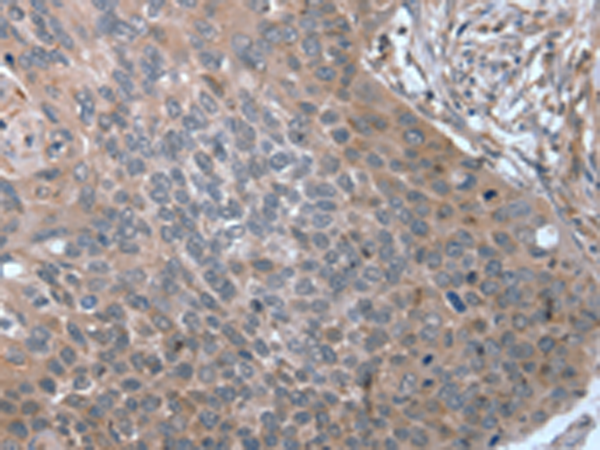

分类: 科研抗体货号: P08782别名: SM22; SMCC; TAGLN1; WS3-10应用: IHC反应种属: Human, Rat